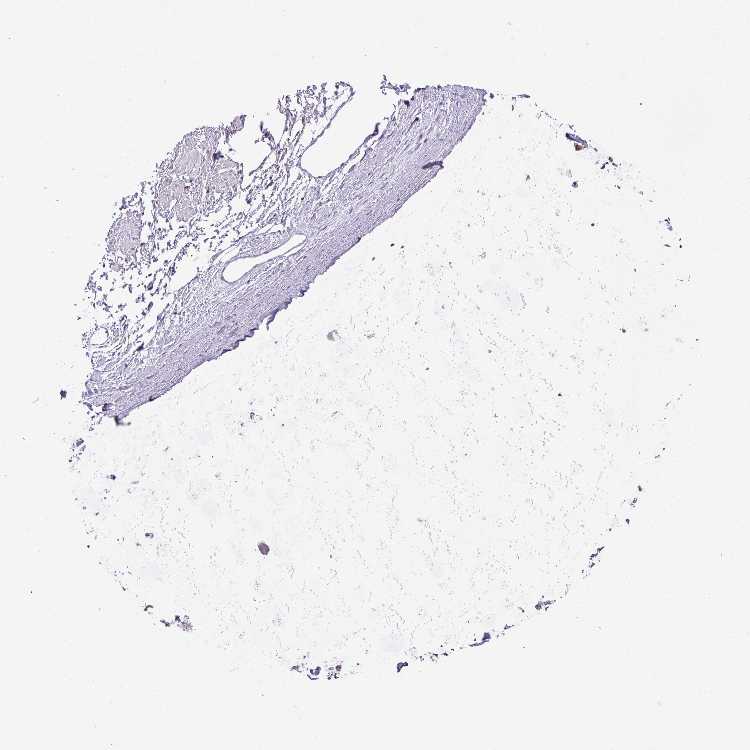

SOFT TISSUE 1 - Antibody stainingi

Antibody staining in the annotated cell types in the current human tissue is reported as not detected, low, medium, or high, based on conventional immunohistochemistry profiling in selected tissues. This score is based on the combination of the staining intensity and fraction of stained cells.

Each image is clickable and will lead to virtual microscopy that enables deeper exploration of all samples and also displays staining intensity scores, fraction scores and subcellular localization as well as patient and tissue information for each sample.

Antibody HPA019085Antibody HPA020456

Chondrocytes Low-

Fibroblasts Not detectedNot detected

Peripheral nerve LowNot detected